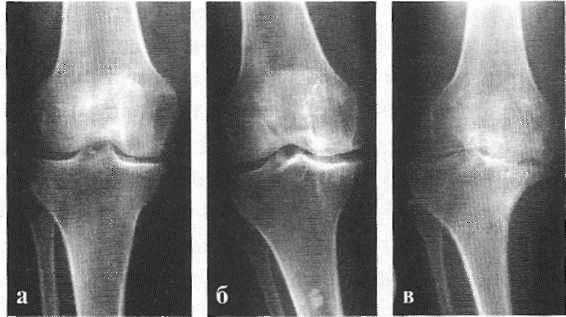

В подавляющем большинстве случаев достаточно осмотра и рентгенограммы коленного сустава в двух проекциях (прямой и боковой). [2] [19] Клинические данные и снимки позволяют определить стадию заболевания.

На ранних стадиях заболевания, при незначительных изменениях в костной ткани, рентгенологическое обследование не настолько ценно. [5] [8] На этом этапе гонартроз возможно диагностировать благодаря артроскопии. [5] [8] Точность метода очень высока, останавливать может только его инвазивный характер и цена.

УЗИ не позволяет произвести четкую визуализацию изменений суставного хряща и внутрисуставных структур. [15] С помощью МРТ можно с 85% точностью выявить изменения костных, хрящевых и мягкотканых структур сустава, а также субхондральной кости. [15] С помощью сцинтиграфии можно оценить метаболическую активность периартикулярной костной ткани.